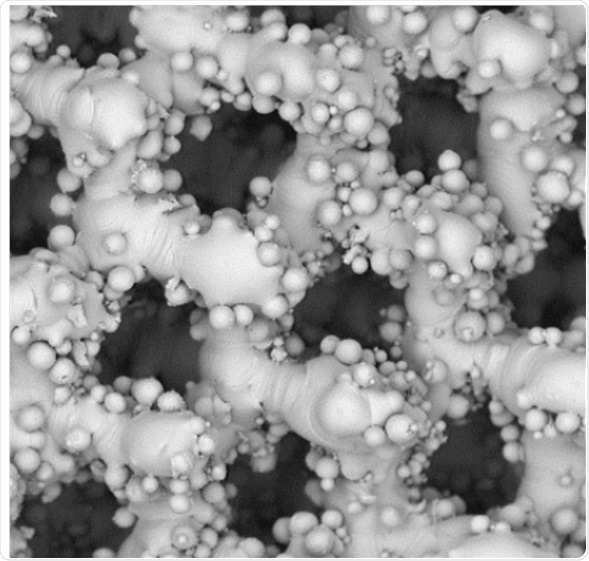

The laboratory used a SEM for this comparison, wherein the growth of human osteoblast (bone matrix cells) on BioOss, a human-like synthetic bone matrix, and on allogeneic bones after 1 week and then 3 weeks of culture, were compared. These images help concluding that the performance of the two materials is equal and confirm the efficiency of highly-processed synthetic grafts.

examples of SEM of human osteoblasts seeded on cancellous bone

Figure 1. Top row: examples of SEM of human osteoblasts seeded on cancellous bone (ACB) after 1 week of cultivation, showing embedded cells in a bone typical extracellular matrix (image magnification 555x and 1300x as indicated). Lower row: After 3 weeks of cultivation an extensive growth of the osteoblasts could be observed on the surface on BioOss® (image magnification 600x and 2840x as indicated). Images adapted1.